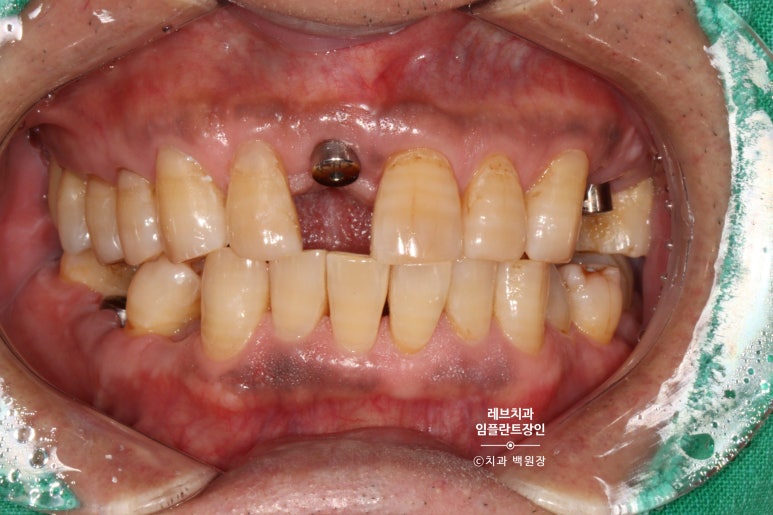

왼쪽 송곳니와 앞니가 흔들리고 고름이 나요.

왼쪽 위 송곳니 (앞니)에서 고름이 나온다는 말씀을 하시던 환자분입니다.

보시면 가만히 있어도 치아와 잇몸 사이에서 고름이 올라오는 것을 보실 수 있어요..

흡연을 좋아하시던 분이었고, 만성 치주염이 심해져서 치주농양까지 진행된 상태입니다.

치과용 파노라마 사진에서도 왼쪽 위 송곳니 주변으로 잇몸뼈가 사라진 것을 보실 수 있는데요,

만성치주염으로 상당히 많은 양의 잇몸뼈가 파괴되었죠.